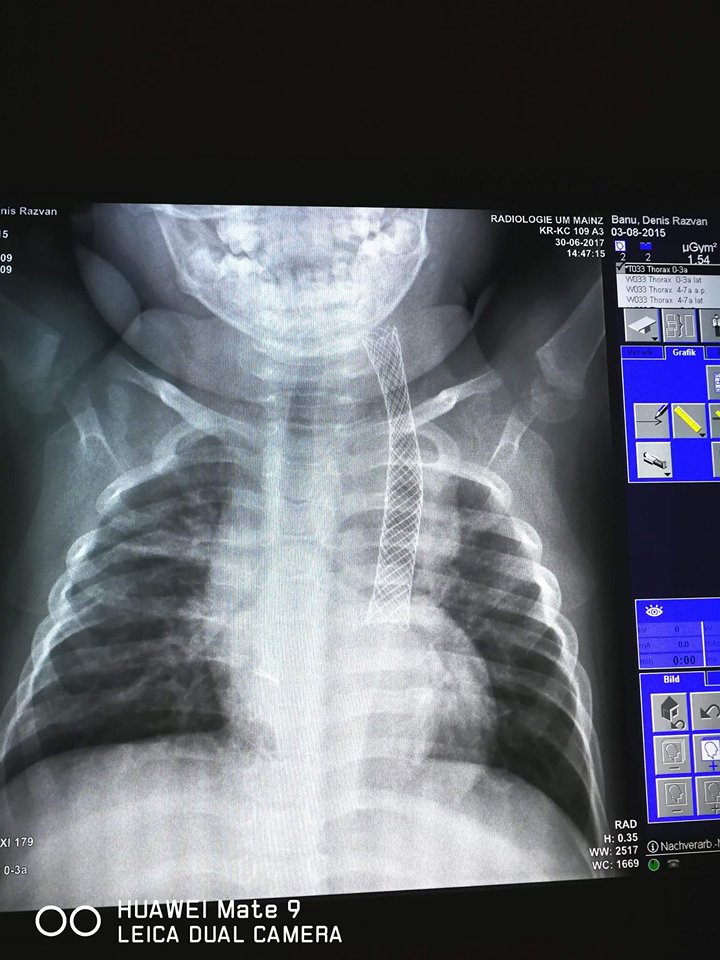

UPDATE: 05.07.2017 Denis a mai trecut printr-o operatie in Germania, este a 17-a operatie! De data aceasta i s-a facut pilorotomie si reconstructie de stomac. De asemenea, s-a refacut refluxul esofagian si s-a pus un nou sten aproape cat esofagul. Medicii din Germania sunt optimisti ca Denis se va intoarce acasa la finalul lunii Septembrie si va putea sa manance ca orice copil.